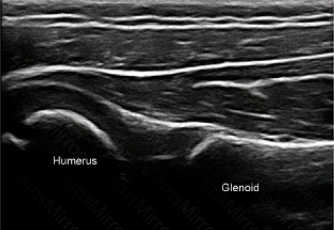

This posterior transverse scan of the shoulder of a 3-year-old boy shows which of the following?